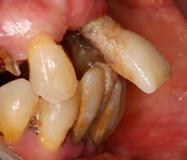

del caso donde podemos observar una enfermedad periodontal agresiva, con gran componente de pérdida

En las Figuras 2-27 se muestra uno de los casos incluidos en el estudio donde se situaron 4 de los implantes que forman parte de la muestra, por lo que hemos creído que era uno de los más representativos.

Figura 2. Imagen radiográfica inicial ósea en la mayoría de los dientes, con un defecto horizontal predominante y varios defectos en cuña en dientes aislados. Figura 3-6. Imágenes de la paciente, portadora de una prótesis removible para las ausencias dentarias presentes, que como vemos se encuentra completamente desadaptada además de con una estética poco adecuada.